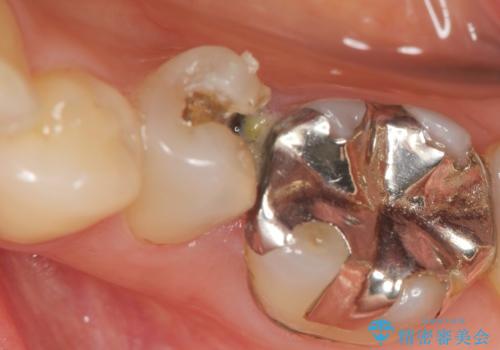

銀歯が外れ、内部に大きな虫歯の再発

- 20年ほど前に治療した虫歯が脱離し、内部には大きな虫歯が認められました。

神経を保存できるよう丁寧に虫歯を除去し、セラミックによる機能回復を計画します。

- 8万円(仮歯・エコノミーemaxクラウン)費用は治療当時の料金となります